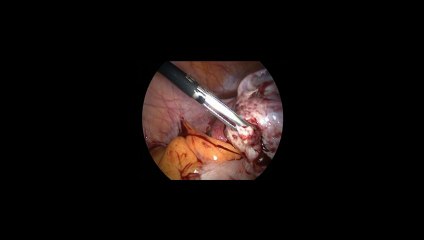

Laparoskopi ile Endometiroma (Çikolata kisti) operasyonu 1 - Prof. Dr. Aydan Biri

Laparoskopi ile Endometiroma (Çikolata kisti) operasyonu 1 - Prof. Dr.